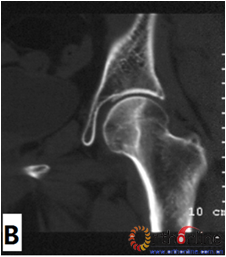

2. 依据SARS后ARCO分期Ⅰ期的ONFH患者(自然进展组)初次普查时的MRI或CT片,选用冠状位正中层面的T1WI(MRI)图像或冠状位二维重建的正中层面的(CT)图像,根据坏死灶占据外侧柱情况分为三型。Ⅰ型:坏死灶占据中央及内侧柱,外侧柱完全保留;Ⅱ型:部分外侧柱被坏死灶占据,部分保留(至少外侧皮质保留);Ⅲ型:坏死带穿透股骨头骨髓与外侧皮质,外侧柱无存留。(图2)

图2-1

图2-2

图2-3

图2 依据股骨头外侧柱存留情况,股骨头坏死的分型。(图2-1)分为Ⅰ型(外侧柱全部存留)(A)MRI图像显示;(B)7年后CT显示股骨头仍未塌陷;(图2-2)Ⅱ型(外侧柱部分保留)(A)MRI显示外侧皮质存留;(B)4年后CT显示股骨头仍未塌陷;(图2-3)Ⅲ型(坏死带穿透股骨头);(A)MRI显示坏死带;(B)2年后股骨头塌陷

Fig 2 According to preservation of the lateral pillar, the necrosis was divided into three types. (Fig 2-1)Type Ⅰ: Whole lateral pillar preserved (A) MRI showing; (B) no collapse occurred seven years later by CT showing. (Fig 2-2)Type Ⅱ: Preservation of the partial lateral pillar, (A) MRI showed the preservation of the lateral cortical bone; (B) no collapse of the femoral head four years by CT. (Fig 2-3)Type Ⅲ: the necrotic line pass through the cortical bone and bone morrow ;(A) MRI showed the necrotic line; (B) collapse of the femoral head occurred two year later.